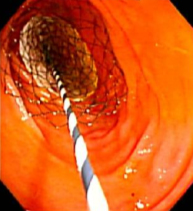

図3. 胃十二指腸閉塞に対する

ステント留置の内視鏡写真

食道、胃、十二指腸の場合には口から内視鏡を、大腸の場合にはおしりから内視鏡を挿入し、消化管閉塞を認めている部位まで内視鏡を誘導します。閉塞部分で再度造影検査を行い、実際の閉塞部位の長さや屈曲状況などを確認します。ガイドワイヤーを閉塞部分より奥まで誘導して、閉塞部分を十分覆う形でガイドワイヤーに沿わせて消化管ステントを留置して、閉塞を解除します。

消化管ステントは針金でできており、留置すると自己拡張力によって徐々に拡張していき、閉塞部分を押し広げていきます。留置後2-3日で多くの場合、完全拡張してきます。それにより癌によって閉塞した消化管を内腔から押し広げ、針金で裏打ちする形となります。